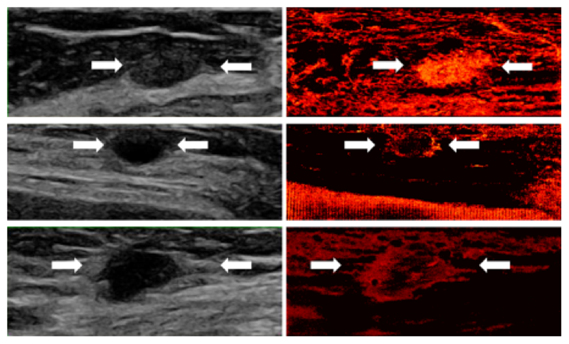

Super-resolution demonstrations in human ultrasound scans

show the vascular characteristics of three types of breast lesions:

- Top (Fibroadenoma - benign): The super-resolved image reveals an oval, well-circumscribed mass with uniform, dense vascularization.

- Middle (Cyst - benign): The recovery highlights peripheral vascular concentration surrounding a round, avascular core.

- Bottom (Invasive Ductal Carcinoma - malignant): An irregular, ill-defined mass with sparse central and dense peripheral vasculature.

Super-resolution vascular imaging of three breast lesions: fibroadenoma (top), cyst (middle), and invasive ductal carcinoma (bottom).